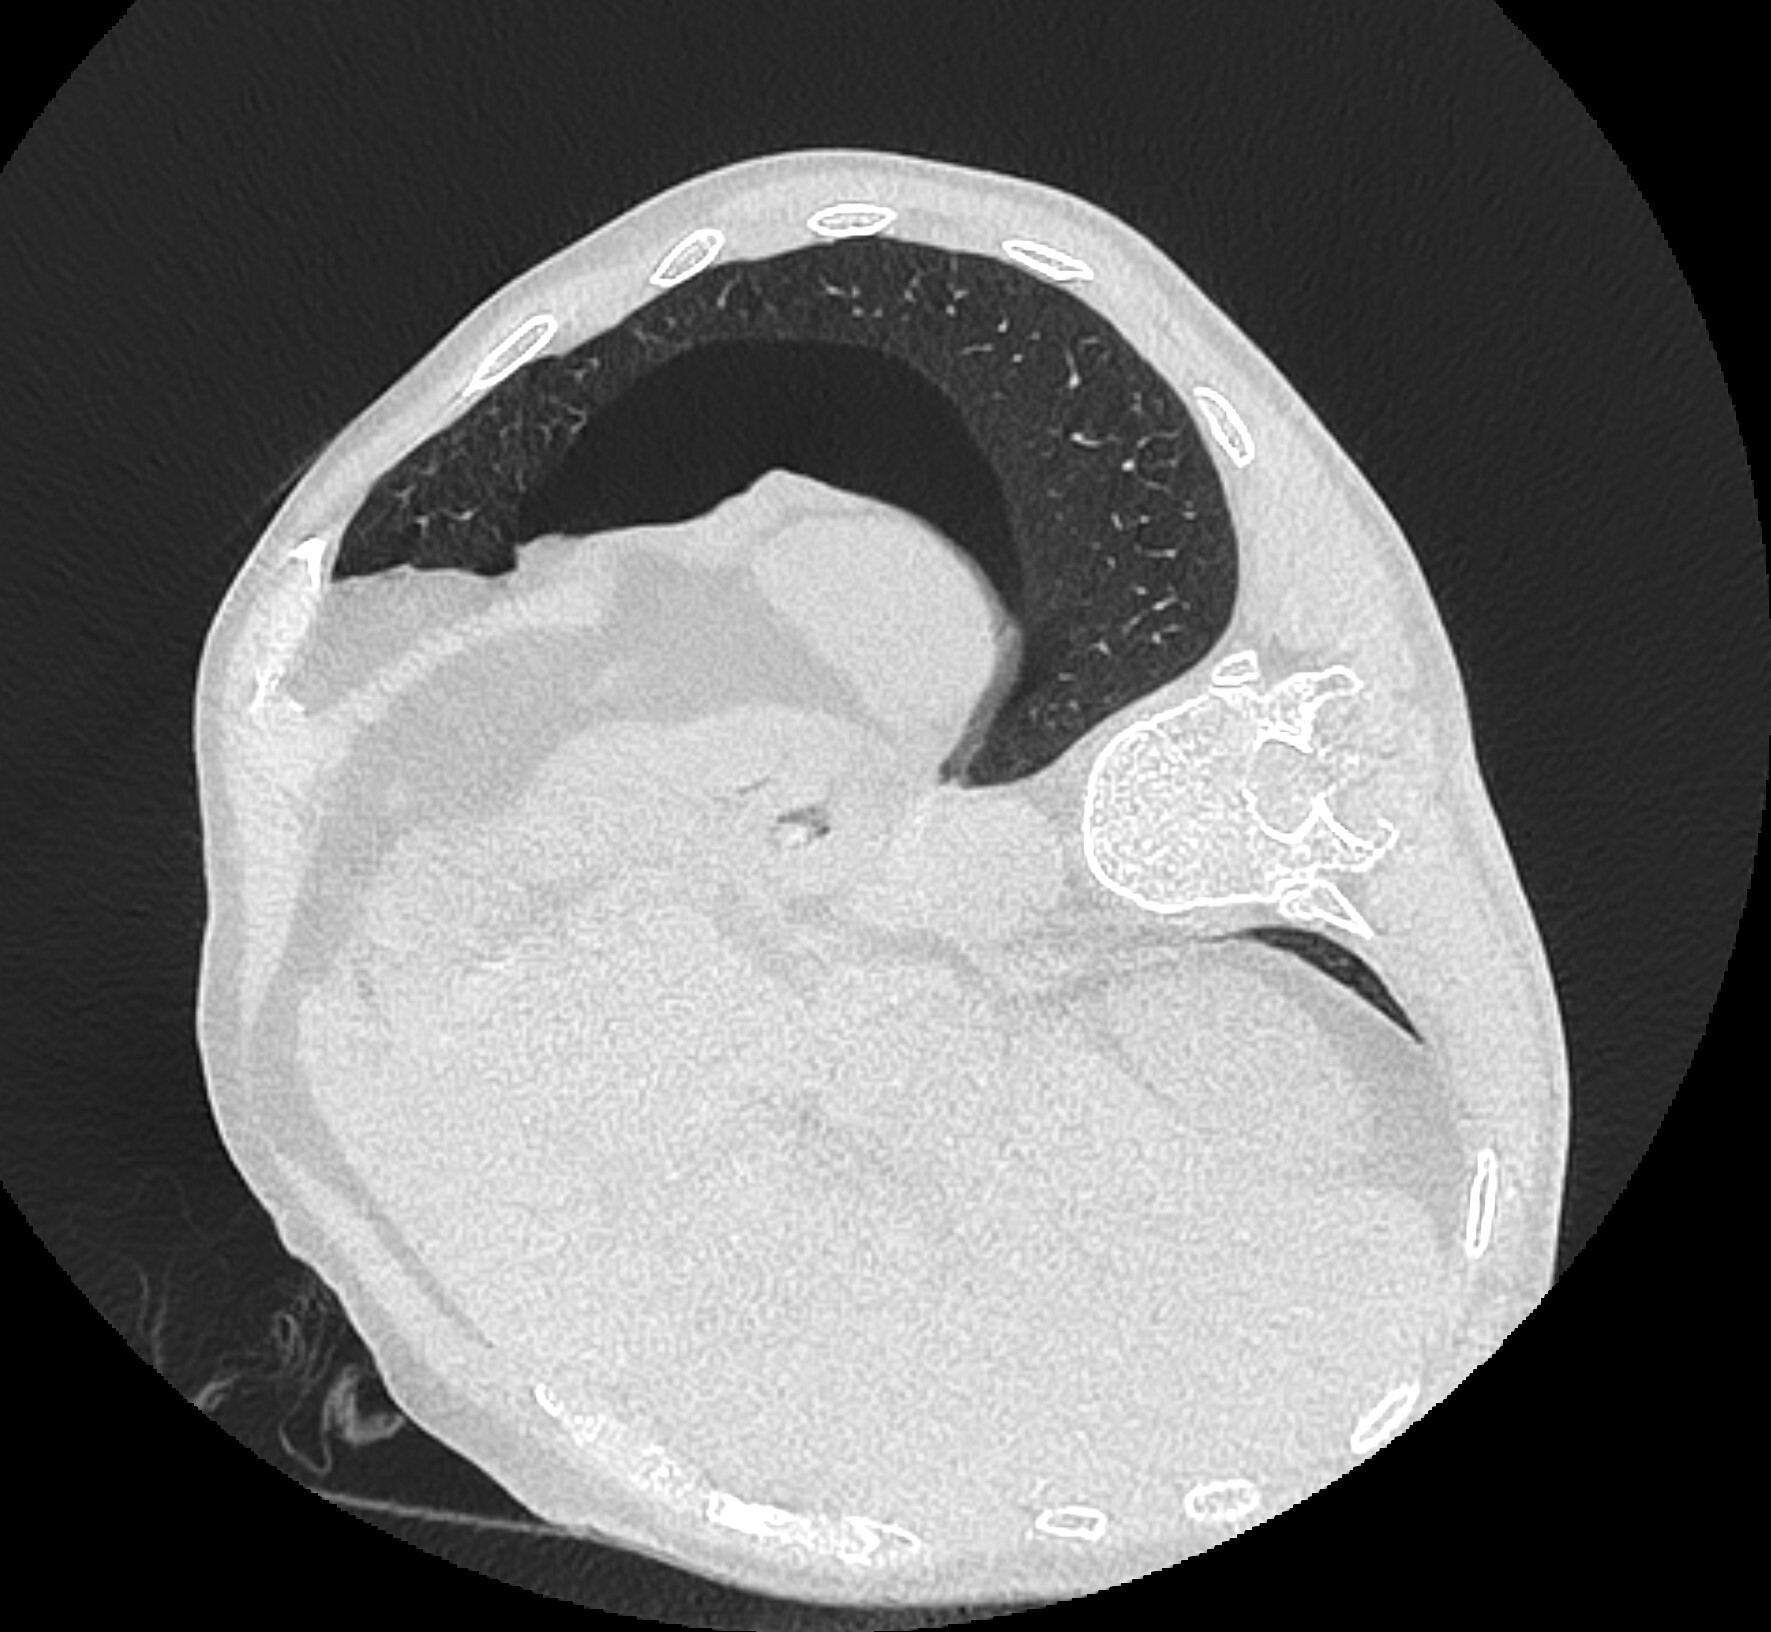

На контроле ещё через 2 часа (т.е. в целом через 4 часа после пункции) пневмоторакс особо не изменился и даже немного уменьшился, что говорит о его стабильности и небольшом рассасывании: